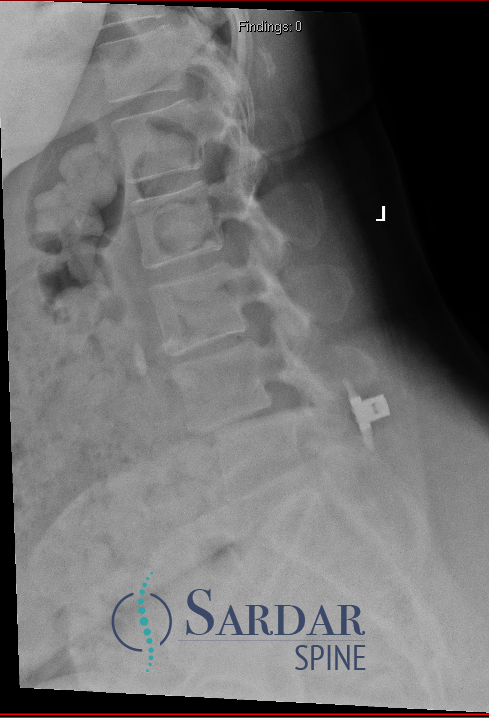

Case 1, Part 2: The patient had a #Vertiflex procedure done elsewhere; symptoms worsened, now can't stand upright, uses walker. Thoughts on her treatment so far? Next steps? #MedTwitter #Orthopedics #orthopedicsurgery #neurosurgery #spine #spinehealth #spinesurgery #scoliosis

55F with back pain and neurogenic claudication. Despite PT and epidural injections, relief is temporary. Difficulty walking long distances due to pain. What treatment would you offer next? #MedTwitter #SpineHealth #NeurogenicClaudication #spine